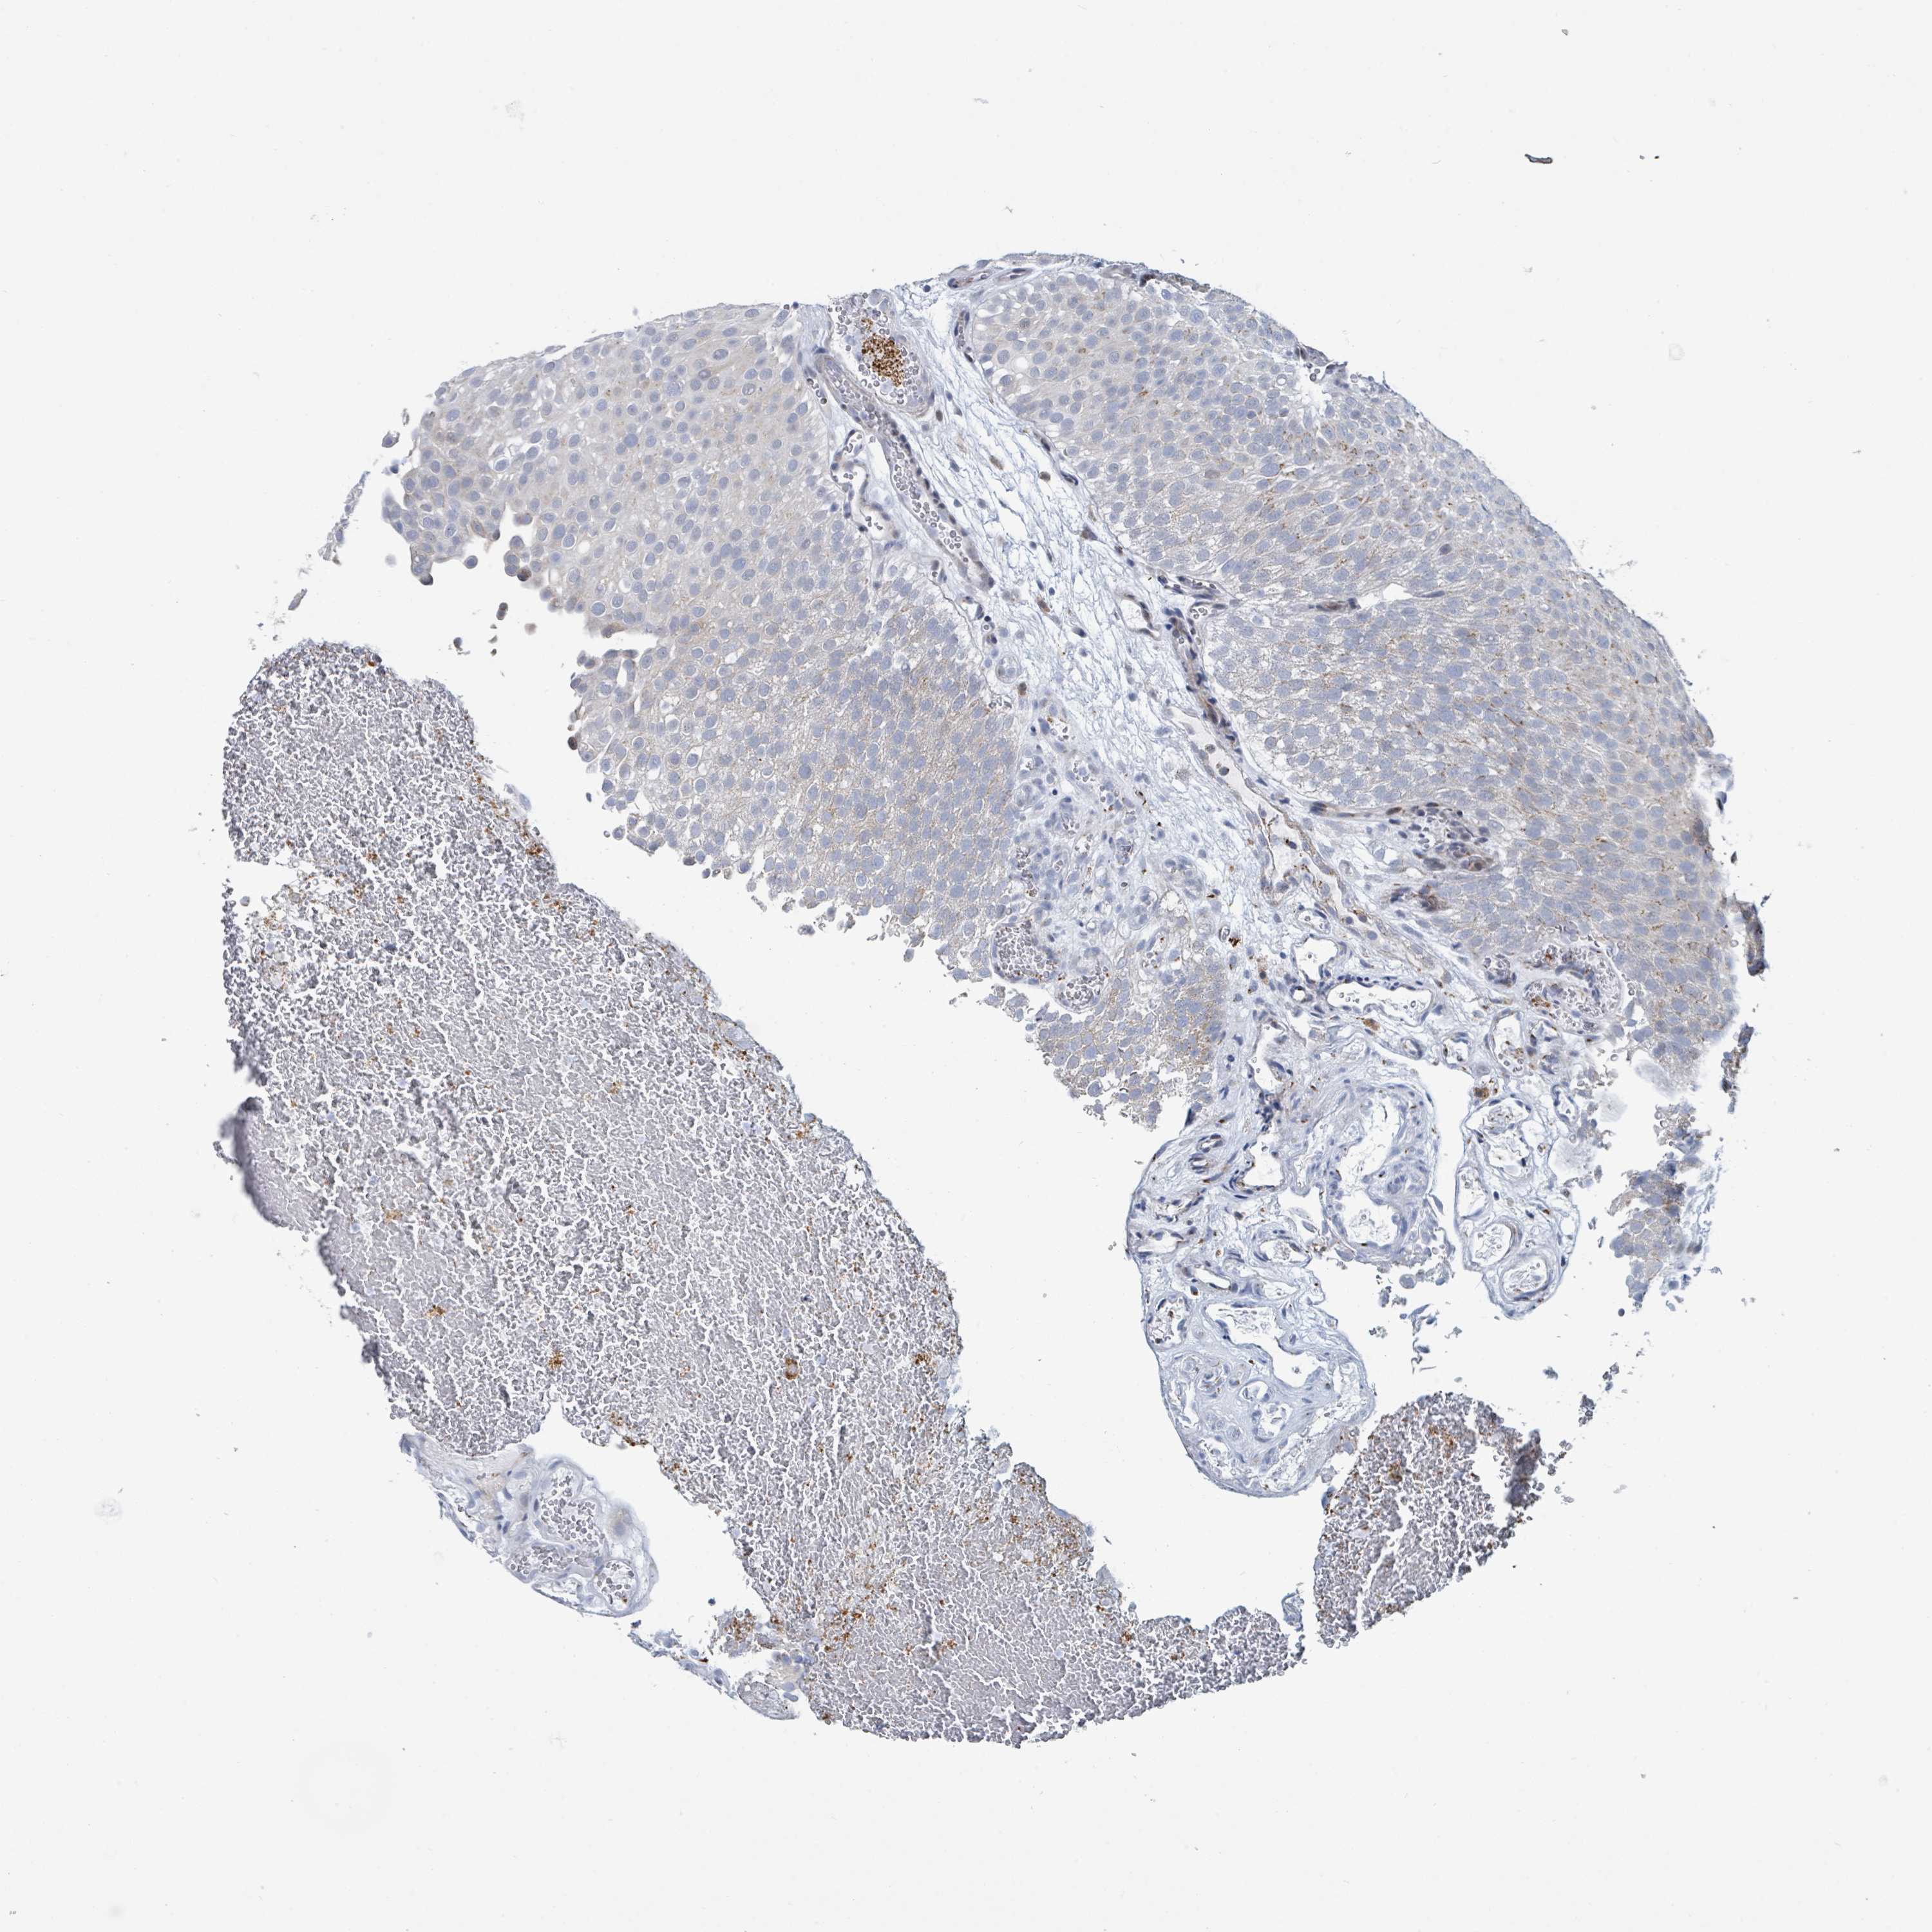

UROTHELIAL CANCER - Protein expressioni

A mouse-over function shows sample information and annotation data. Click on an image to view it in a full screen mode. Samples can be filtered based on level of antibody staining by selecting one or several of the following categories: high, medium, low and not detected. The assay and annotation is described here.

Note that samples used for immunohistochemistry by the Human Protein Atlas do not correspond to samples in the TCGA dataset.

Antibody stainingi

Antibody staining in the annotated cell types in the current human tissue is reported as not detected, low, medium, or high, based on conventional immunohistochemistry profiling in selected tissues. This score is based on the combination of the staining intensity and fraction of stained cells.

Each image is clickable and will lead to virtual microscopy that enables deeper exploration of all samples and also displays staining intensity scores, fraction scores and subcellular localization as well as patient and tissue information for each sample.

Antibody HPA041575

Antibody HPA048098

Staining

High

Medium

Low

Not detected

Intensity

Strong

Moderate

Weak

Negative

Quantity

>75%

75%-25%

<25%

None

Location

Nuclear

Cytoplasmic/membranous

Cytoplasmic/membranous,nuclear

Urothelial carcinoma, High grade

Urothelial carcinoma, Low grade

Urothelial carcinoma, NOS